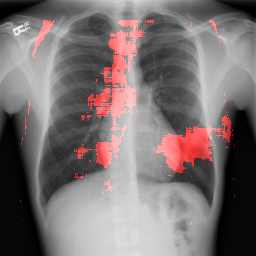

4.2 Localization

For any diagnostic task, it is desirable to gain intuitive understanding of why a certain classification decision is made rather than being a black box method. In other words, it is desirable to distinguish features that contributed most to certain abnormality in the entire chest X-Ray. There are various ways of achieving this goal [25, 30, 31, 32]. The method used in [25] is the simplest, where a patch is occluded in the image to measure its impact on the eventual classification confidence score. We have used this method to find the regions in the image responsible for a certain abnormality detection. As a representative example, we have used cardiomegaly and pulmonary edema which occur in heart and lung areas respectively. The localization scheme described in section 3.4 is followed with a patch size of pixels taking lowest values of probabilities. Instead of gray level occlusion as in [25] we found that black level occlusion works better for CXRs. This is due to the fact that the CXRs themselves are mostly gray level and occlusion of the same level does not hide much information compared to the neighborhood.

4.2.1 Cardiomegaly Localization

The localization of abnormalities in cardiomegaly examples are shown in Fig. 7. Here, of the image area is shown which has the highest sensitivity. It can be observed from the figures that the network is indeed most sensitive to the region where the heart is larger than a normal heart. We have performed this experiment on cardiomegaly and normal images and found this localization to be consistent for most examples. There is not much functional difference between a normal and cardiomegaly example other than the fact that the heart in cardiomegaly is larger than a normal heart. Given the fact that the normal images could also have various size of heart depending on the age or physical attributes of a patient, we found this level of localization sensitivity to be remarkable. Also interesting is the fact that the standard rule based features like CTR and CTAR take into account the relative size of heart and lung to determine if there is cardiomegaly present or not. In the DCN localization experiment, we see counter-intuitively that most of the signals contributing to the softmax score are coming from the heart only. This means that there are characteristic features in the shape of the heart and its surrounding regions that alone is sufficient to detect cardiomegaly. The lung and its relative size are probably less important features when trying to detect cardiomegaly. This observation is counterintuitive and needs to be explored further in future work.

8 Additional Examples of Localization

In this section we show more examples of localization. Few localization samples are shown in Fig. 11. It can be observed that, in the CXRs with Cardiomegaly (Fig. 11(a) and (b)) a fine localization around the heart is observed. In the normal CXRs (Fig. 11(c) and (d)) such localization is not observed. Rather the lowest probabilities are spread out in the CXR image. It is interesting to note that, the localization algorithm gets low probability where the heart is enlarged during cardiomegaly, but the proportion is small compared to the localization in other areas of normal CXRs. In order to observe the performance of the heat map we computed histograms of heat maps of each of the 100 CXRs in the test set for Cardiomegaly detection and average histograms are shown in Fig. 11(e) and (f) for CXRs with Cardiomegaly and normal CXRs, respectively. It is to be noted that, the histograms include both success and failure cases. It can be observed that, for CXRs with Cardiomegaly the classifier is highly sensitive toward Cardiomegaly detection even under occlusion. This indicates that, the classifier primarily looks for local features in a CXR instead of some feature that is spread out in the entire CXR. However, the classifier is not sensitive toward normal CXRs under occlusion. Rather, the probabilities are spread out in the probability spectrum. After that, we analyzed the failure cases where the classifier is unable to classify the image correctly. Two such examples of failure cases are shown in Fig. 12. The localized CXR shown in Fig. 12(a) contains Cardiomegaly whereas the classifier detects it as normal. However, the localization shows that it localizes around heart quite well despite the in accurate classification. On the other hand, Fig. 12(b) shows an example of normal image which has been classified as Cardiomegaly by the classifier. There is stronger localization around the hear that that is observed for normal images as in Fig. 11(c) and (d), however, like those images the localization is spread out.